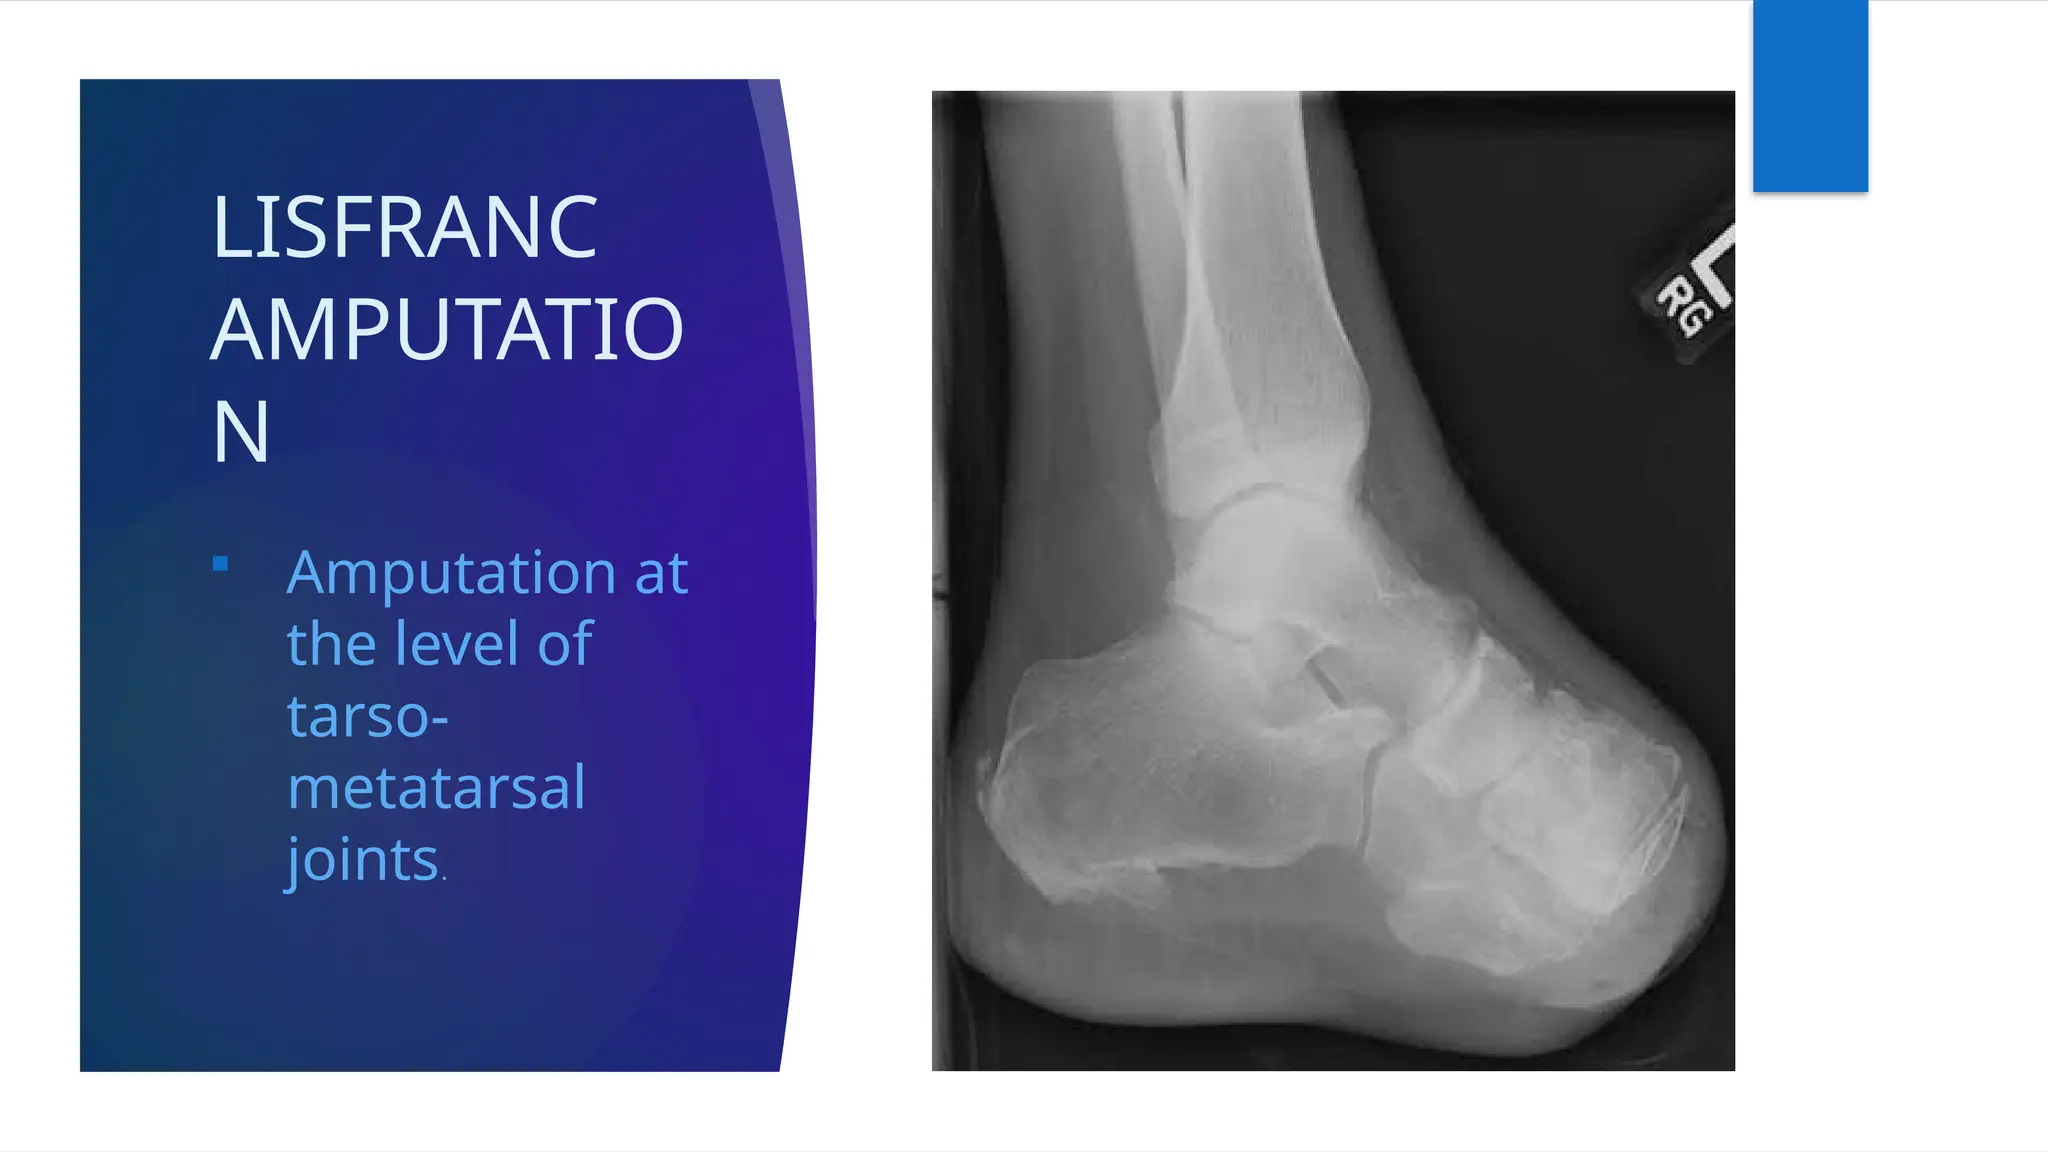

LISFRANC

AMPUTATIO

N

 Amputation at

the level of

tarso-

metatarsal

joints.

LISFRANC AMPUTATIO N  Amputation at thelevel of tarso- metatarsal joints.